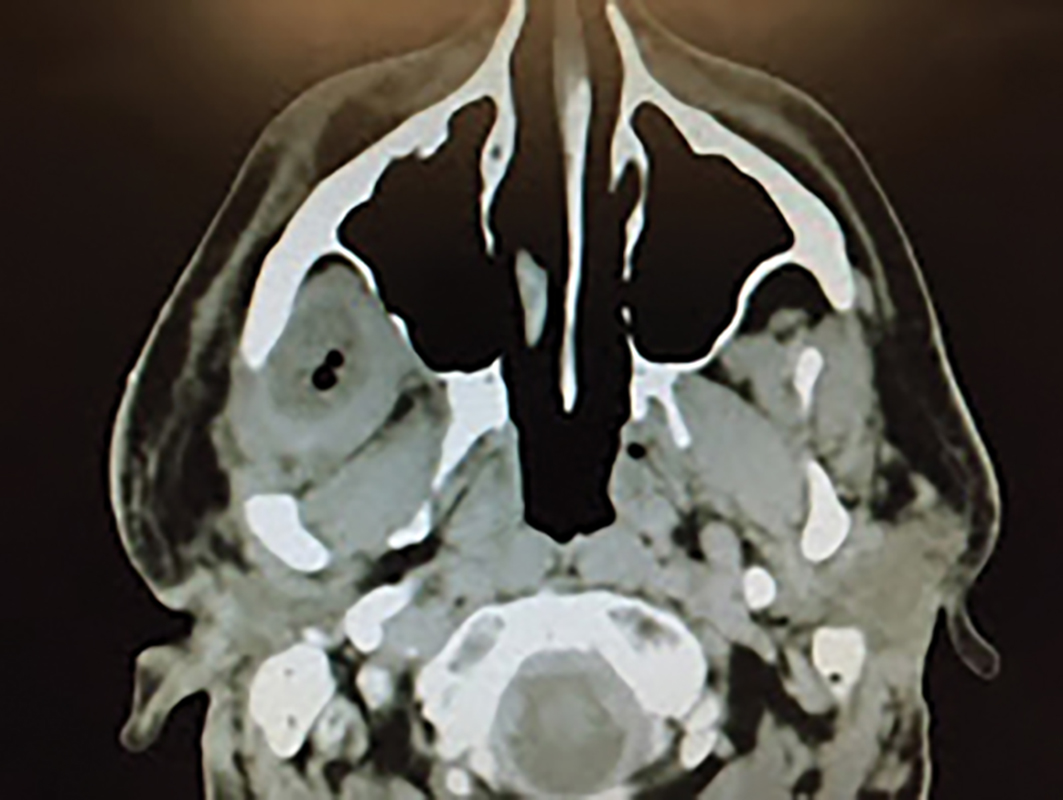

The Largest Nasopalatine Duct Cyst: A Case Report and Literature Review

Abstract The nasopalatine duct cyst is the most common non-odontogenic developmental cysts. This case report presents a nasopalatine duct cyst in a patient with a history of orofacial pain over one year with multiple doctor visits and only limited success. This nasopalatine duct cyst is the largest reported to date. It was treated with enucleation … Read more